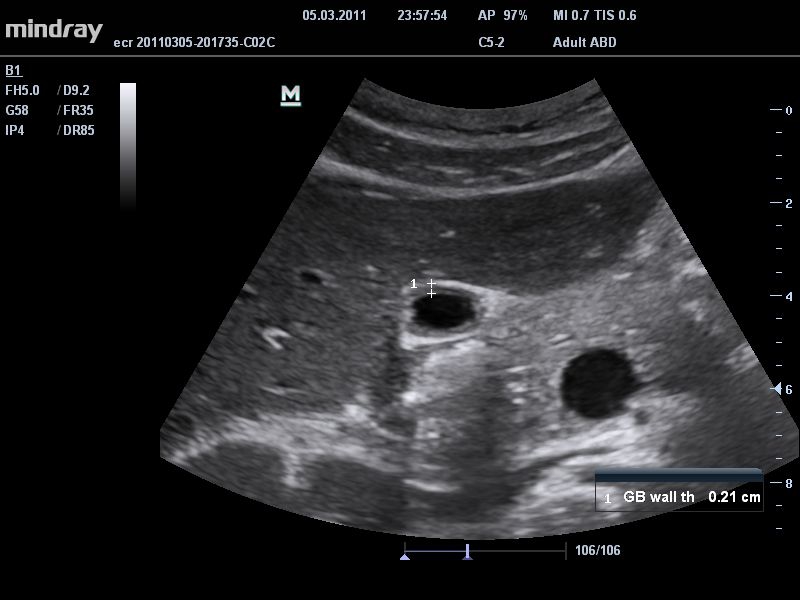

Mindray DC-T6

Ультразвуковая система Mindray DC-T6 – это инновационный аппарат для проведения высокого уровня диагностики с качественной визуализацией и широким спектром применения. Платформа рекомендована для использования в коммерчески многопрофильных медицинских учреждениях и государственных лечебных клиниках.

B-режим, Двухмерное сканирование:

Да

• THI со сдвигом фазы: увеличивает четкость визуализации желчного и мочевого пузыря и повышает отношение сигнал-шум.